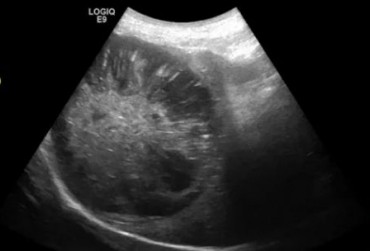

Pies, golden retriever 6mcy. Strunowe ciało obce w jelicie czczym.

24 czerwca 2019

Wojciech Atamaniuk

Czytaj więcej